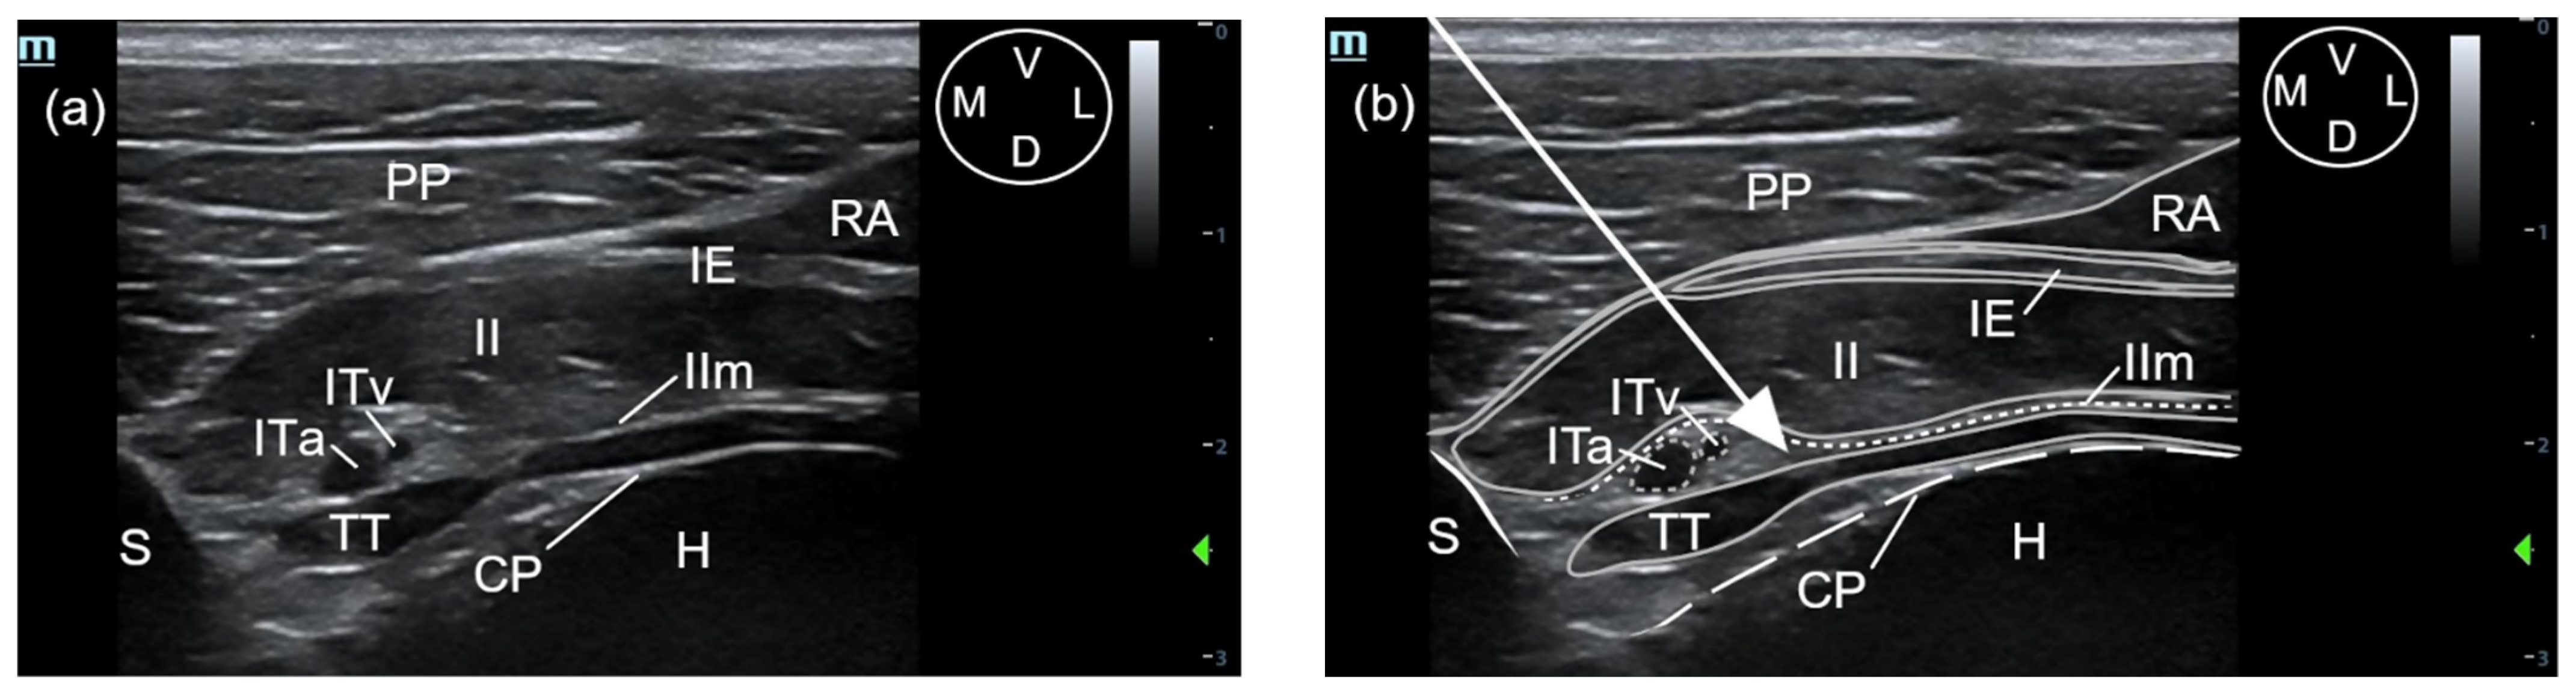

A 63 mm, 22-gauge spinal needle (BD Spinal Needle; BD Medical, Franklin Lakes, NJ, USA) was inserted in a ventromedial-to-dorsolateral direction with an in-plane technique. The needle was advanced through the pectoralis profunda, rectus abdominis, external and internal intercostal muscles, and internal intercostal membrane until the tip was positioned into the TTP, ventral to TT muscle and laterally to the internal thoracic artery and vein (Figure 2 and Figure 3). To confirm the presence of the needle tip into the target plane, a small amount of the injectable solution was slowly administered until a small pocket of fluid was visualized between the internal intercostal membrane and the transversus thoracis muscle. Then, the remaining volume corresponding to that side of the thorax was injected (Figure 3). If the solution injection did not reach the target plane, the tip of the needle was redirected and all the procedure was repeated. In all the injections, the quality of the needle tip ultrasound visualization was evaluated (Appendix A). The procedure was repeated on the contralateral side.

The sonographic landmarks were visualized in all hemithoraxes. The visualisation of the needle tip into the TTP was scored as good in 12 out of 16 injections and poor in 4 out of 16 injections. Fat was easily visualized into the TTP in all injections, facilitating the identification of the correct plane. In all injections, the formation of a pocket of fluid between the TT and internal intercostal membrane could be recognized (Figure 3).

Figure 3. Ultrasound image of the pocket of fluid formation after the injection of a methylene blue-lidocaine solution using the t-TTP approach, at the level of the fifth interchondral space. The pocket of fluid is delimited by the dotted line. CP, costal pleura; D, dorsal; IE, external intercostal muscle; II, internal intercostal muscle; IIm, internal intercostal membrane; L, lateral; M, medial; Nt, needle tip; Pk, pocket of fluid, PP, pectoralis profunda muscle; RA, rectus abdominis muscle; S, sternum; TT, transversus thoracis muscle; V, ventral.